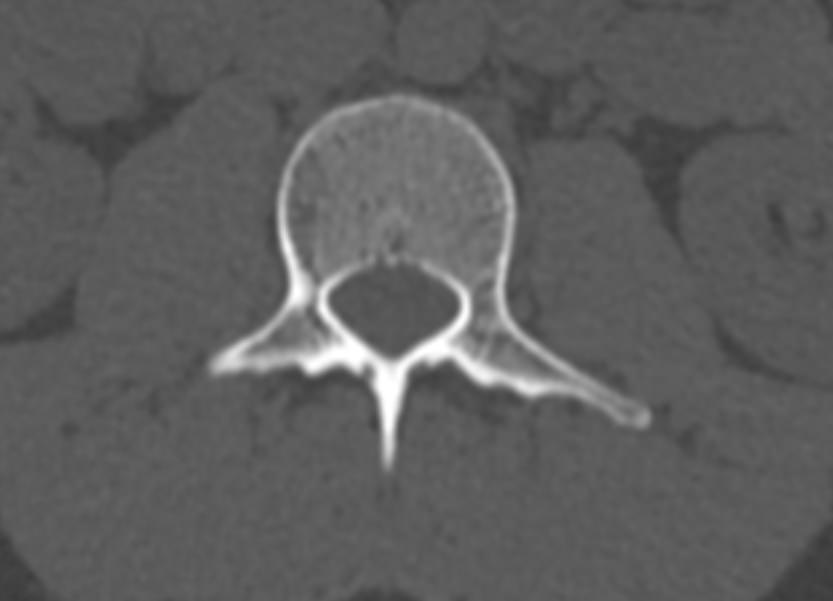

Для диагностики даже незначительных патологических изменений в различных отделах позвоночника, особенно в случае распространенного поражения, применяется один из современных наиболее информативных методов обследования – мультиспиральная компьютерная томография всего позвоночника. Методика основана на использовании проникающей способности рентгеновских лучей через органы и ткани человека и позволяет получить подробное изображение всех структур позвоночного столба. В комплексное обследование входит исследование шейного, грудного, пояснично-крестцового отделов позвоночника и копчика.

В медицинских центрах «Доступная медицина» сканирование всего позвоночника выполняется на новейших мультиспиральных компьютерных томографах последнего поколения TOSHIBA AQUILION в различных модификациях. Особенностью данных аппаратов является их способность проводить от 64 до 128 тончайших срезов одномоментно с минимальной толщиной от 0,5 мм.

Увеличенное количество высокочувствительных детекторов, которыми оснащены томографы, позволяет получать послойные снимки высокого качества с большой скоростью. Эта особенность данных аппаратов обеспечивает быстроту выполнения сканирования. При этом пациент получает минимальную дозу облучения, что имеет важное значение, особенно при такой обширной зоне исследования, как позвоночный столб.